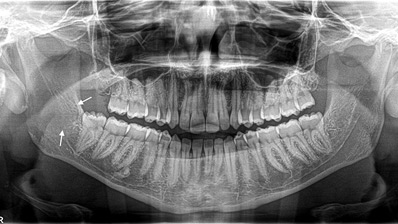

Management of Severe Obstructive Sleep Apnea With Maxillomandibular Advancement Surgery

Abstract Obstructive sleep apnea (OSA) is a common disorder that causes patients to temporarily stop or decrease their breathing repeatedly during sleep. OSA has been associated with increased morbidity and mortality rates as well as decreased quality-of-life. Certain patients with maxillomandibular abnormalities, such as mandibular retrognathia, suffer from moderate to severe OSA. Although continuous positive … Read more